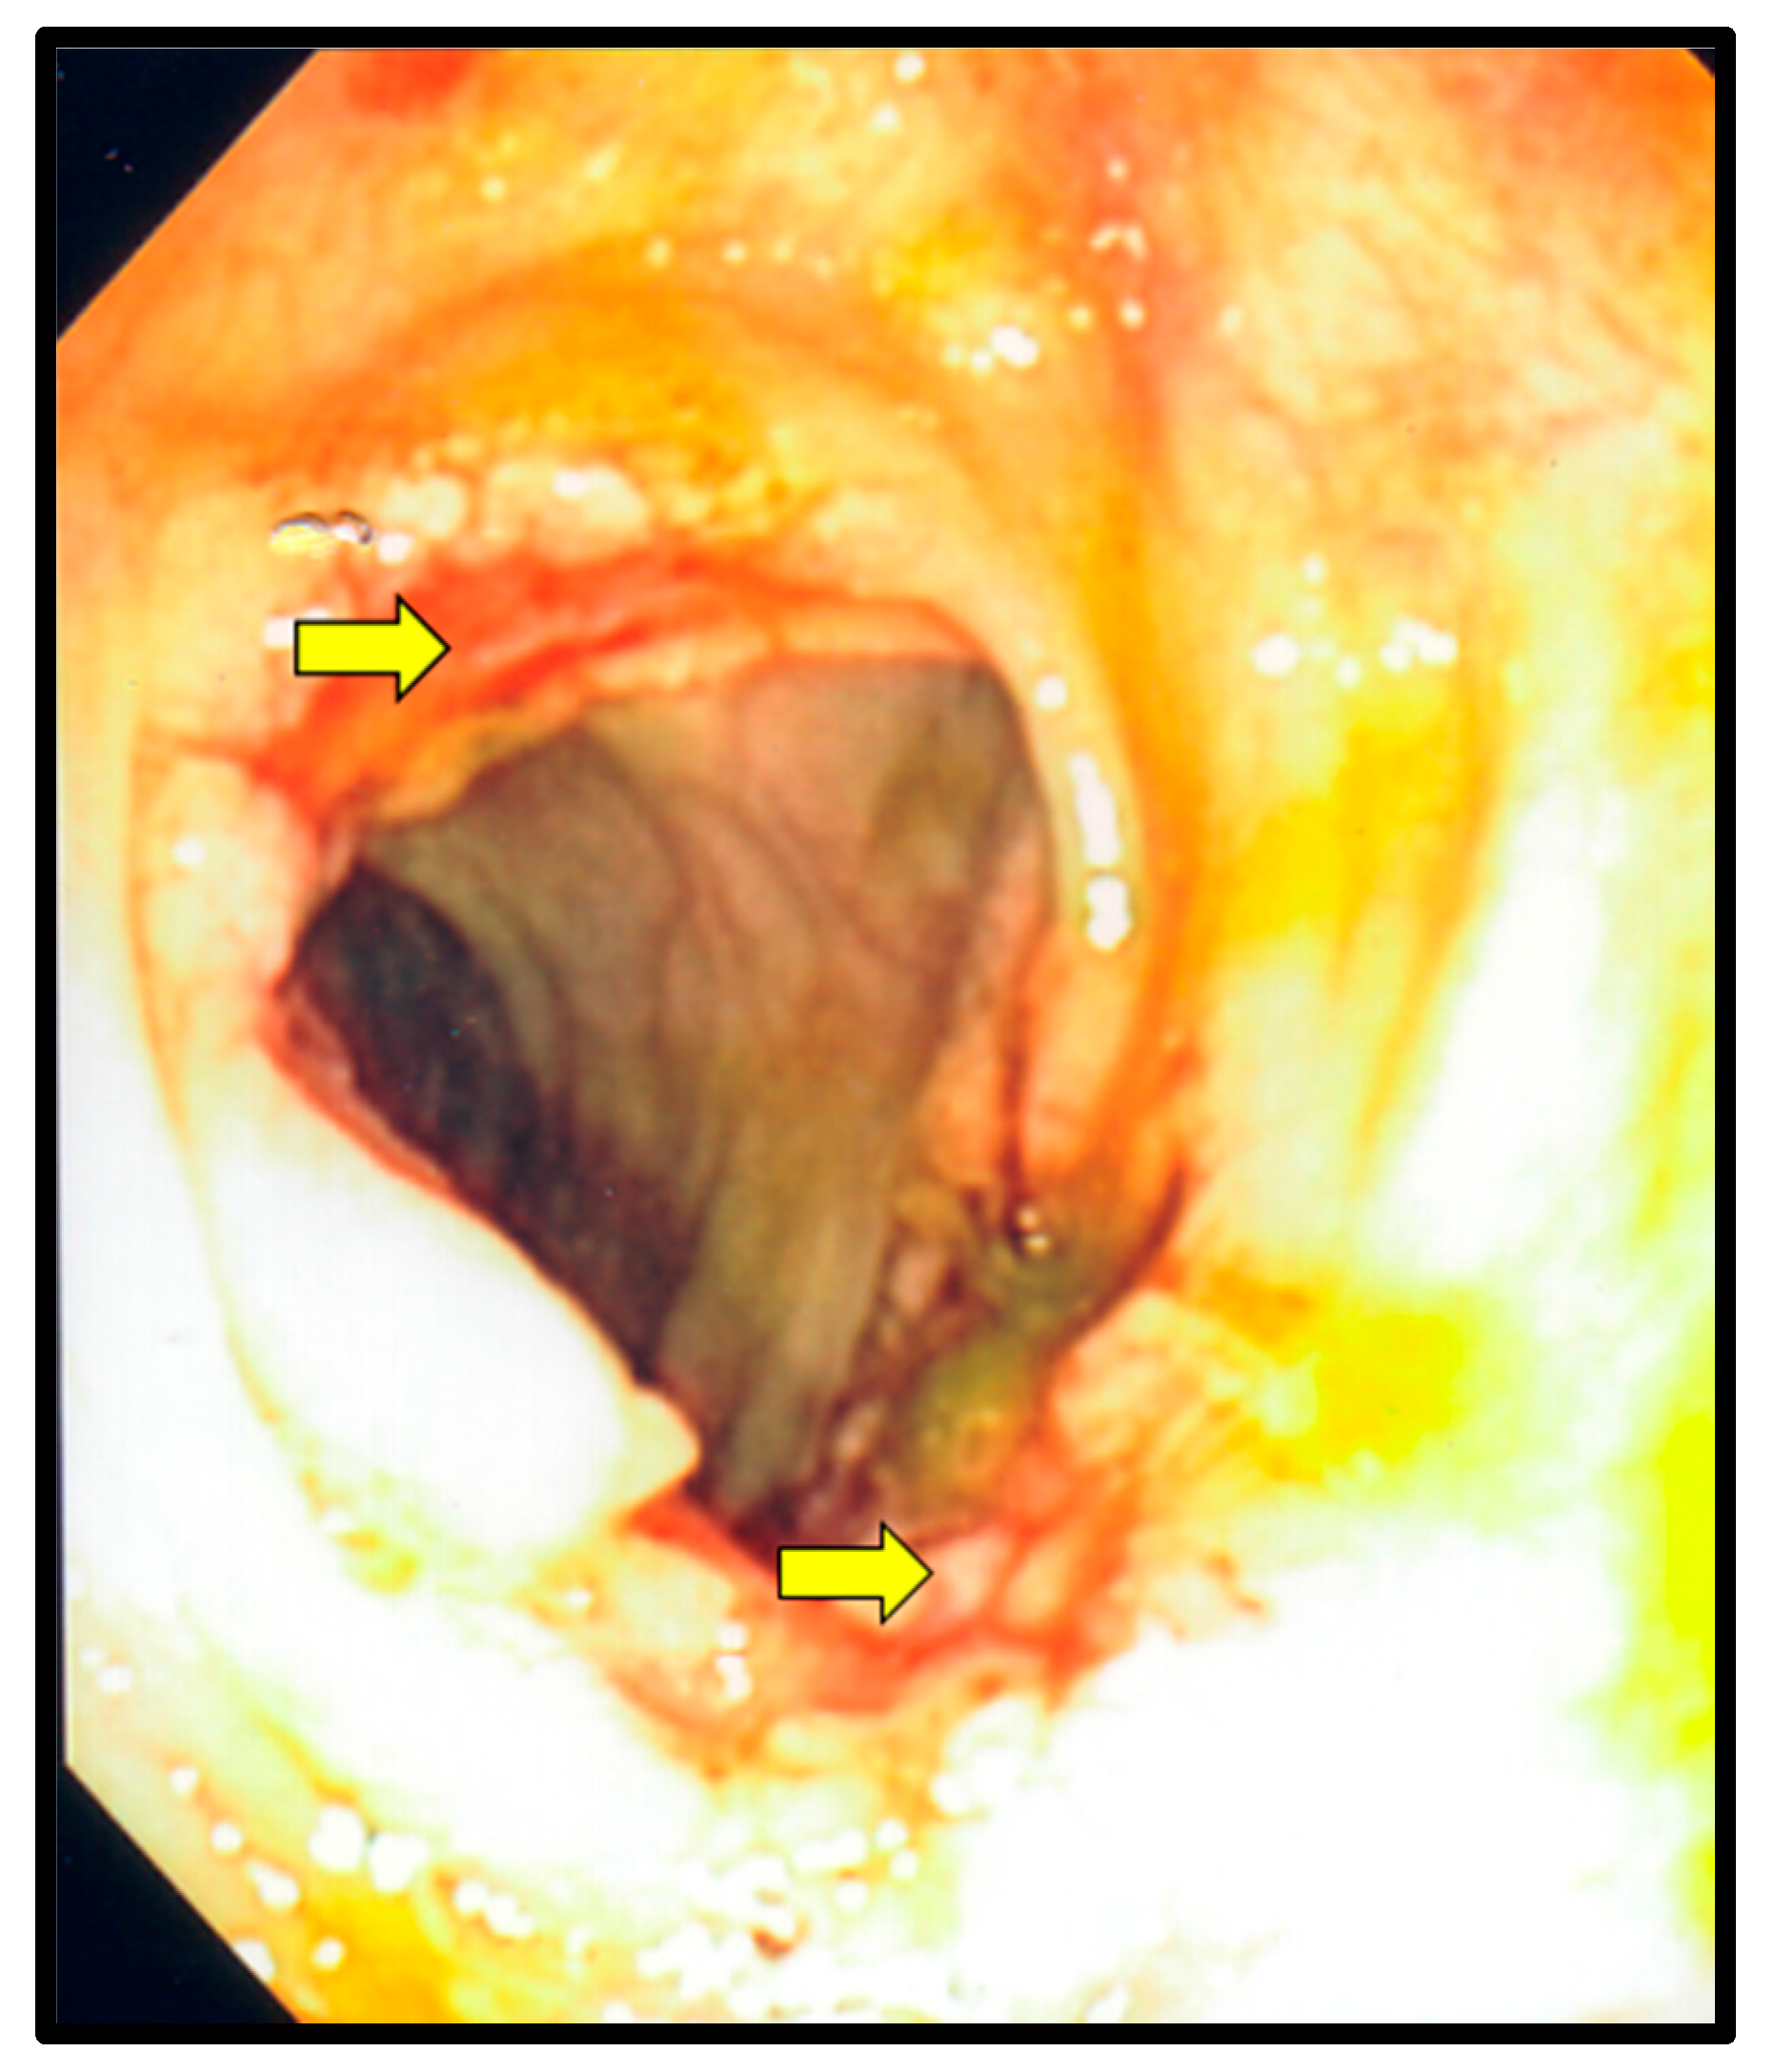

Figure 3.

Colonoscopy. The yellow arrows point to ulcerations in the transverse colon, which were secondary to Histoplasmosis and cytomegalovirus co-infection.